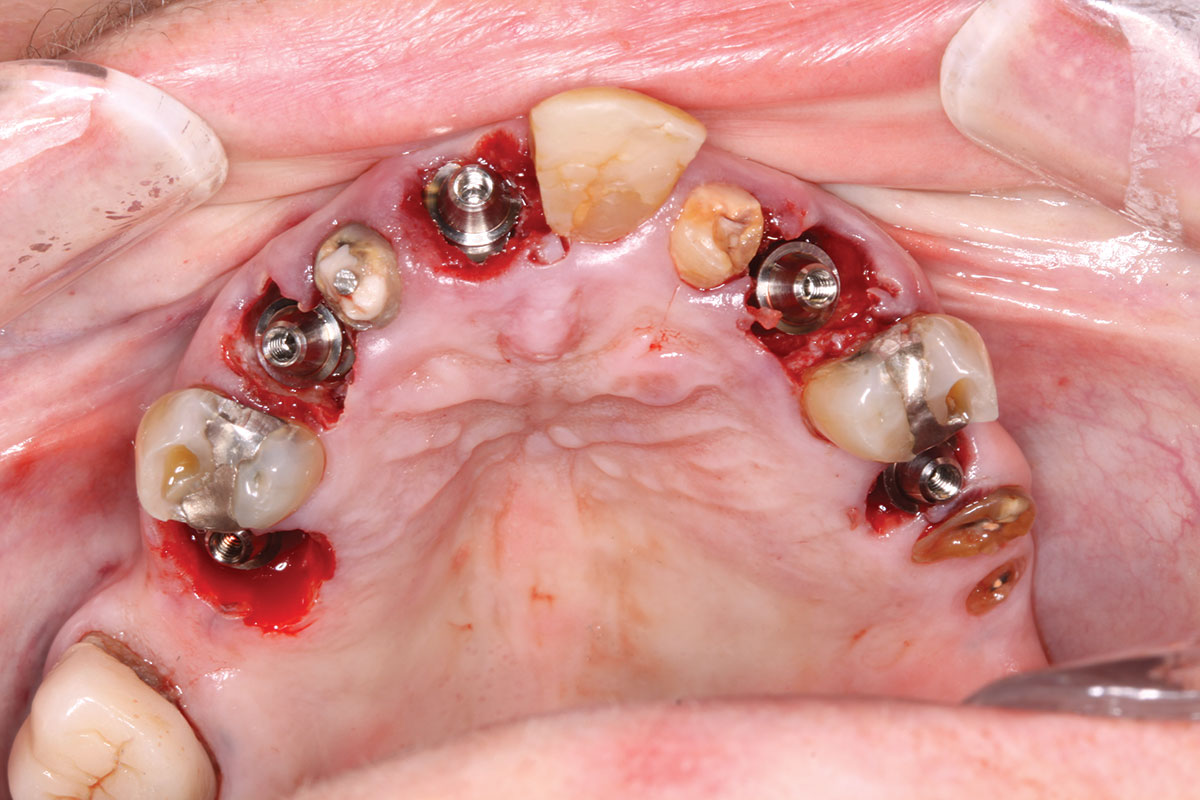

Fig 14. All implants, multi-unit abutments, and scan gauges in place.

Figure 14

Fig 15. Completion of maxillary flapless immediate implant surgery and placement of multi-unit abutments.

Figure 15

A week later the patient presented for surgery for extraction and replacement of her existing maxillary dentition with implants and a screw-retained provisional implant restoration. Teeth Nos. 2, 4, and 6 through 11, 13, and 14 were carefully extracted with attention paid to retaining site dimensions. Immediate implants were inserted into sites Nos. 4, 6, 8, 11, and 13 with high insertion torques in excess of

40 Ncm. Subsequently, multi-unit abutments were placed on all the implants and torqued to 30 Ncm, and scan gauges were placed on implant Nos. 8 and 11 (Figure 12 and Figure 13).

A maxillary intraoral scan was obtained with a digital scanner capturing the two remaining teeth in sites Nos. 5 and 12 and the scan gauges on implants Nos. 8 and 11. Subsequently, teeth Nos. 5 and 12 were extracted. Scan gauges were placed on implants Nos. 4, 6, and 13. At this time, another intraoral scan was captured of all the scan gauges on the five implants with the surrounding soft tissues (Figure 14 and Figure 15).